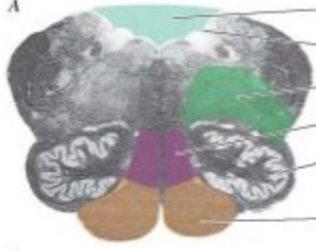

lower medulla

knowt flashcard image